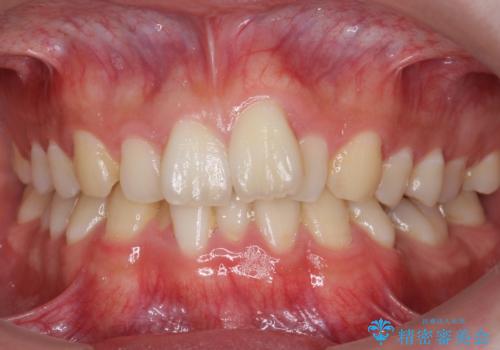

前歯のがたつき・すれちがい咬合を非抜歯で。流行の、格安マウスピースでは難しい、ワンランク上の治療

- 前歯のがたつきを主訴に来院。

左下の奥歯を後ろに移動して、中に入ってすれちがっていた小臼歯を並べました。